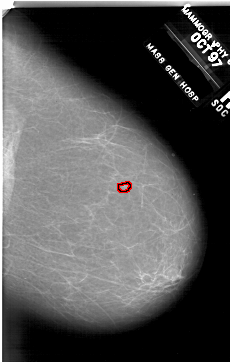

A_1911_1.LEFT_CC

LEFT_CC LINES 6631 PIXELS_PER_LINE 3991 BITS_PER_PIXEL 12 RESOLUTION 43.5 NON_OVERLAY

FILE: A_1911_1.RIGHT_CC.OVERLAY

TOTAL_ABNORMALITIES 1

ABNORMALITY 1

LESION_TYPE MASS SHAPE LOBULATED MARGINS CIRCUMSCRIBED

ASSESSMENT 3

SUBTLETY 2

PATHOLOGY BENIGN

TOTAL_OUTLINES 1

BOUNDARY